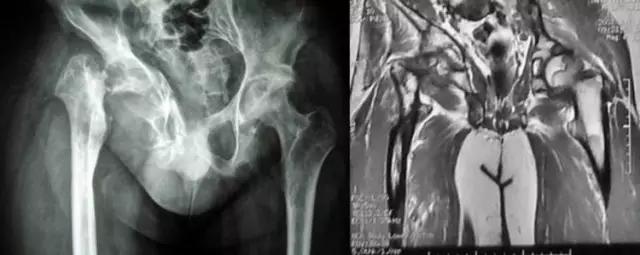

只能显示骨的改变,对早期膝关节炎等临床常见疾病的诊断意义不大,但"骨质增生"的诊断报告却常常影响病人一辈子!

下图是同一个病人的MRI照片,MRI显示的内容更多,包括骨与软组织等,很多早期的、细微的病变都能清晰显示,其诊断报告对病人造成的影响也更大!